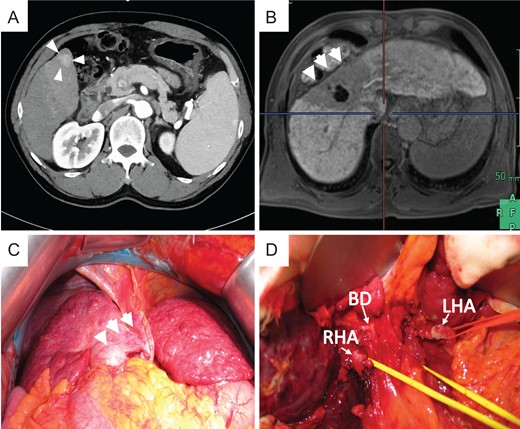

The patient was a 60-year-old man who had been diagnosed with HCV-related LC and HCC (Table 1). In 2014, this patient underwent CIRT with a total of 60 Gy (relative biological effectiveness) given in four fractions for HCC in S4 and was in complete remission (CR). In 2015, multiple HCC was observed on CT (Fig. 3A). After treatment with TACE, he met the Milan criteria and underwent LT. Preoperative magnetic resonance imaging with gadolinium-ethoxybenzyl-diethylenetriamine penta-acetic acid (EOB-MRI) revealed atrophy in the CIRT area and hypertrophy in the left liver (Fig. 3B).

Preoperative photograph and intraoperative images of case 2. (A) New lesion in S6 on preoperative CT. Atrophy was noted in the CIRT area, and hypertrophy was noted in the left liver on preoperative EOB-MRI (B) and intraoperative images (C). (D) Severe tissue adhesion on the hepatic hilar resulted in difficulties during adhesiolysis.

During surgery, strong atrophy of the liver parenchyma was found in the irradiated area (Fig. 3C). Tissues adjacent to the irradiated area were also strongly adhered. During dissection of the right side in the liver hilum, the right hepatic artery (RHA) was injured due to inflexible conglutination (Fig. 3D). We sutured and closed the bleeding point of the RHA and decided to separate the RHA without detachment between the RHA and bile duct. Carefully, the liver was retrieved after we successfully secured the common bile duct, left hepatic artery (LHA), PV and HV. This case is also transplanted with left lobe graft. We reconstructed the middle hepatic vein and left hepatic vein (MHV–LHV) in the recipient to the MHV–LHV in the donor by continuous sutures with 4-0 Prolene, the left branch of the PV in the recipient to the left branch of the PV in the donor by continuous sutures with 5-0 Prolene, and the LHA in the recipient to the LHA in the donor by interrupted sutures with 8-0 Prolene using microscopy.